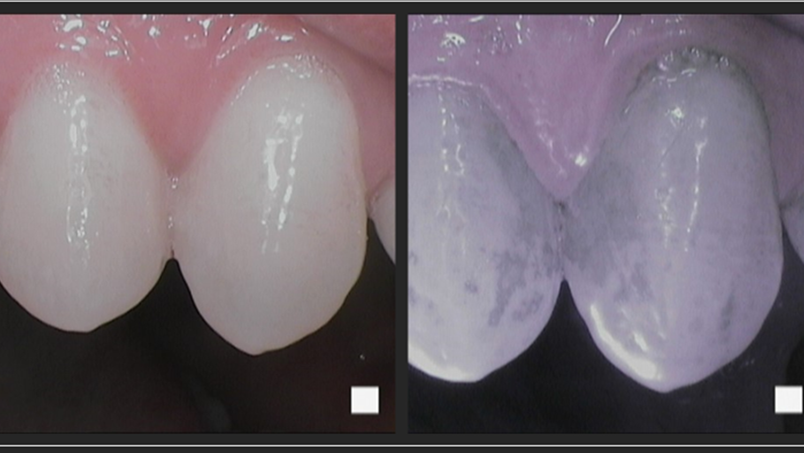

In her bachelor's thesis from the Faculty of Medicine at the University of Helsinki, “Oral Mucositis – Antibacterial Dual Light in the Treatment of Oral Mucositis,” medical student Jessica Hentilä explores the effects of antibacterial photodynamic therapy (aPDT) and antibacterial blue light (aBL) as local treatments on mucositis ulcers.3

Hentilä's research evaluates the efficacy of dual-light therapy against Streptococcus oralis, a common bacterium in the oral microbiome. The study indicates that antibacterial dual light, a combination of aPDT and aBL, not only effectively targets streptococcal infections found in mucositis-induced ulcers, but it simultaneously provides red light therapy.

According to Dr. Tommi Pätilä, thesis advisor on Hentilä’s project and specialist in pediatric heart and organ transplantation surgery, the reduction of oral bacterial load in the mouth promotes mucosal wound healing, concurrently reducing the risk of local and systemic infection complications common in cancer patients. This is an important addition to the conventionally applied red light therapy.3